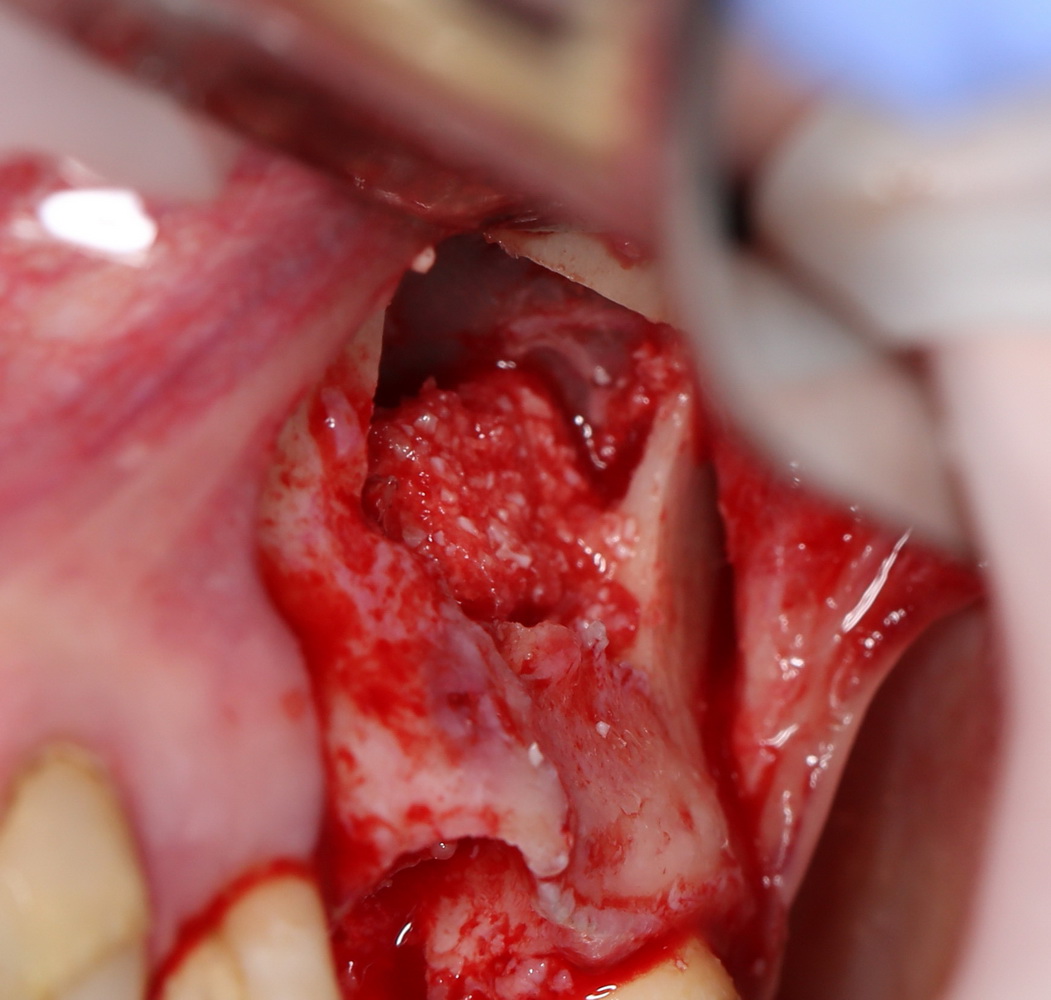

Для проведения операции остеопластики нам необходим донорский участок для забора или аутокостной стружки, или аутокостного фрагмента (графта). Нередко для этого выбирается область с самым удобным для хирурга доступом, создается отдельная рана. На мой взгляд, лучше путь область будет не самая удобная, но, желательно, доступная через рану основной операции. Да, мы усложняем работу, но делаем ее результат более простым и безопасным по ряду причин:

а для бокового отдела нижней челюсти — сам Б-г велел все делать через одну рану: